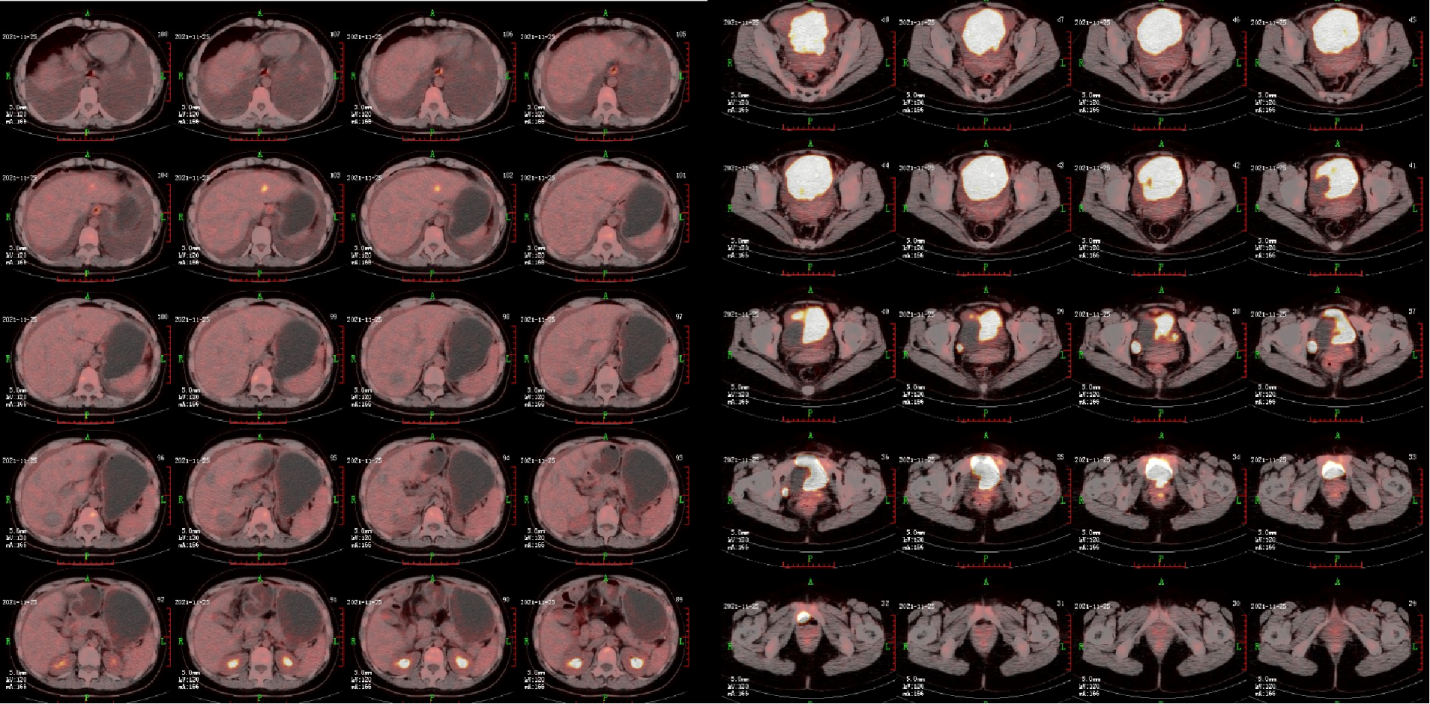

患者行PETCT检查,提示横结肠癌肝转移治疗后,肝S2新增高代谢病灶,约1.4cm*1.2cm,双侧卵巢转移,左侧最长径约25cm,右侧最长径约20cm,中等量腹水(图3)。